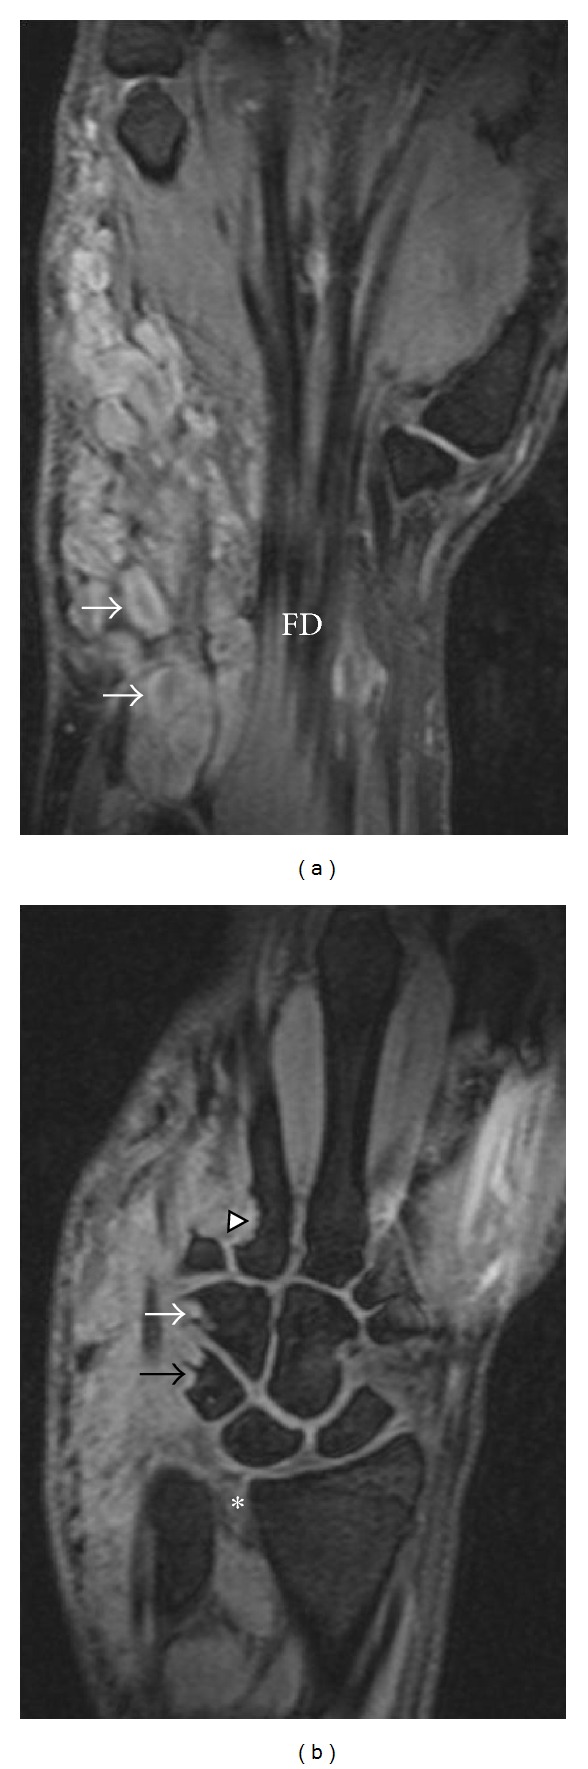

Figure 3.

Coronal T2-weighted wrist MRI with fat suppression—(3a) anterior section: multilobulated mass abutting flexor digitorum longus (FD). Target signs (white arrows). (3b) Posterior section: remodeling of triquetrum (black arrow), hamate (white arrow), and proximal metacarpal (arrowhead). *distal radioulnar joint widening.